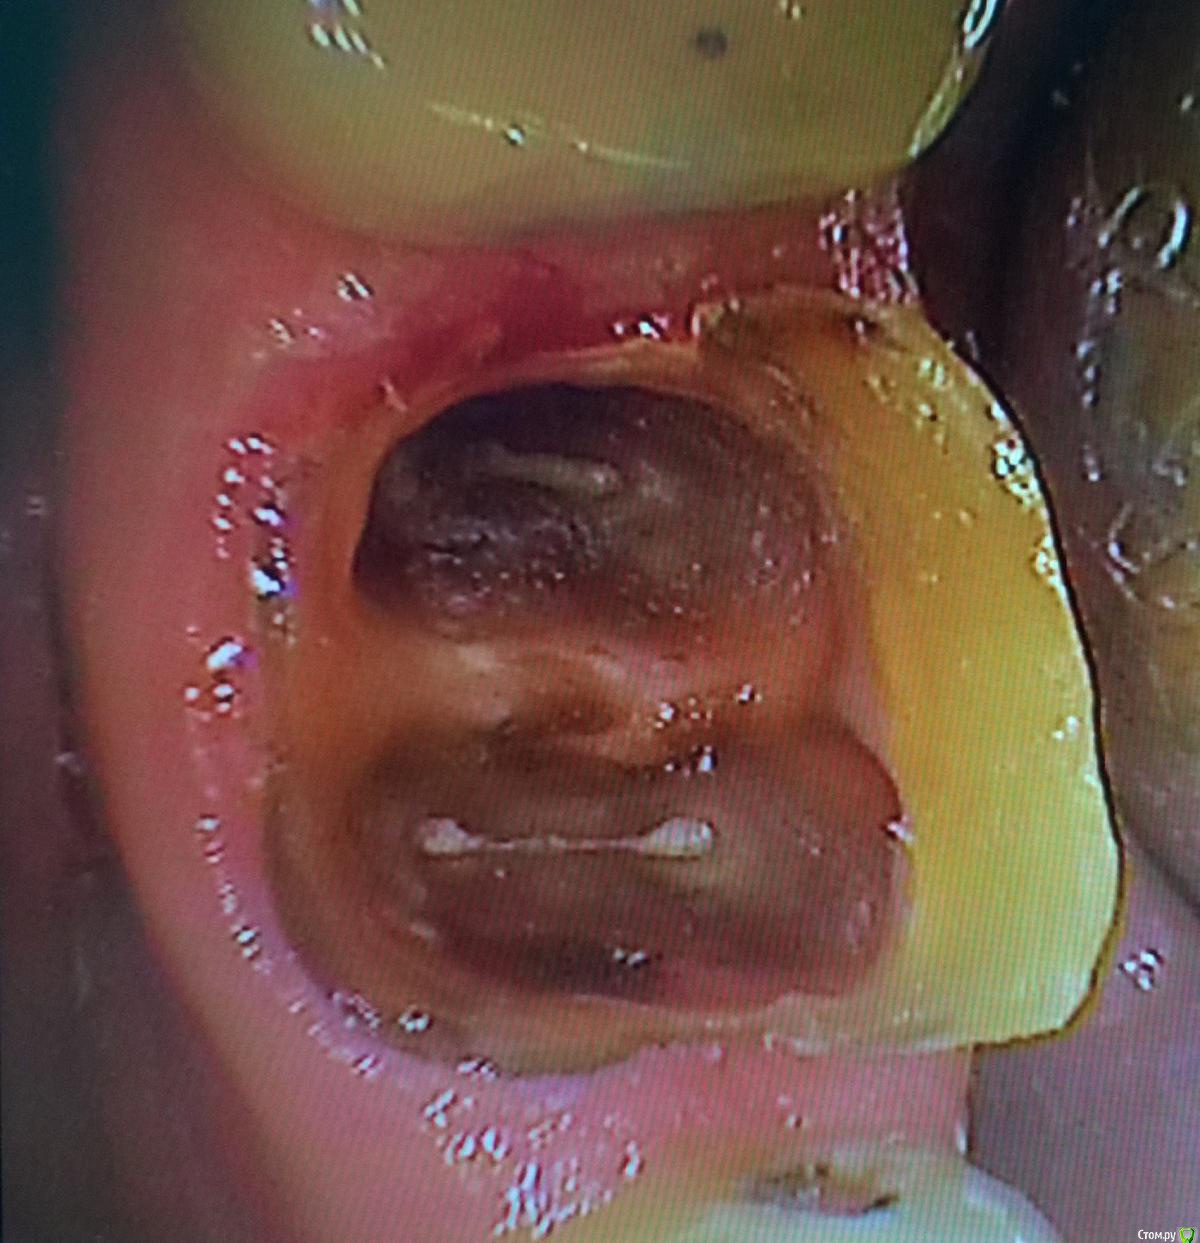

krokomot Опубликовано 27 февраля, 2015 Автор Поделиться Опубликовано 27 февраля, 2015 Удаляйте лучше. Зачем вам проблемы с этим пациентом в будущем?Обновлено. Добавляю недостающее фото удалил после повторной ревизии обнаружилась перфа на дистальной стенке, ниже уровня устья. 1 Ссылка на комментарий

chervoncevdaniil Опубликовано 28 февраля, 2015 Поделиться Опубликовано 28 февраля, 2015 Обновлено. Добавляю недостающее фото под коронкой.jpgудалил после повторной ревизии обнаружилась перфа на дистальной стенке, ниже уровня устья.Дистальный корень без проблем удалился?много пилили кости? Ссылка на комментарий

krokomot Опубликовано 28 февраля, 2015 Автор Поделиться Опубликовано 28 февраля, 2015 Дистальный корень без проблем удалился?мно,го пилили кости?Сразу распилил перегородку между корней, убрал все тонкие части, аккуратно выдавил медиальный корень, а потом елеватором дистальный через перегородку)) Повредилась незначительно только вестибулярня стенка возле медиального корня и только верхняя треть. 1 Ссылка на комментарий